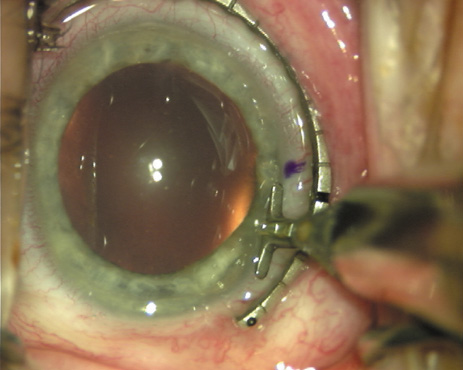

ways. Our preferred method makes use of a modified Fine-Thornton fixation

ring (Nichamin Fixation Ring and Gauge; Mastel Precision, Storz, Rhein

Medical). This instrument serves to fixate and position

the globe in order to optimize incision placement, as well as to delineate

the extent of arc to be incised. One visually extrapolates from

the limbus to marks on the surface of the ring. Each incremental mark

is 10 degrees apart, and bold hash marks (180 degrees) opposite

to each other serve to align and center the incision over the steep

meridian. This approach obviates the need to ink and physically mark

the cornea. If one desires, particularly when first gaining experience

with LRIs, a two-cut RK marker may be used to place ink marks upon the

cornea to show the exact extent of arc that is to be incised, in conjunction

with the fixation ring/gauge (Fig. 4). Alternatively, various press-on markers are available, such as

with the fixation ring/gauge (Fig. 4). Alternatively, various press-on markers are available, such as

those made by Rhein Medical (Dell-Nichamin Marker, Nichamin-Kershner

Marker, or the Ruminson Marker) (Fig. 5). ASICO and other instrument companies offer a full line of dedicated

markers, rings, and blades for performing LRIs.  Fig. 4. The Nichamin Fixation Ring and Gauge serves to both fixate the globe and

delineate the extent of arc to be incised; a two-cut radial marker may

be used to mark the extent of arc to be incised, and the Mastel Nichamin

Force AK Diamond Blade with preset depth of 600 microns. Fig. 4. The Nichamin Fixation Ring and Gauge serves to both fixate the globe and

delineate the extent of arc to be incised; a two-cut radial marker may

be used to mark the extent of arc to be incised, and the Mastel Nichamin

Force AK Diamond Blade with preset depth of 600 microns.